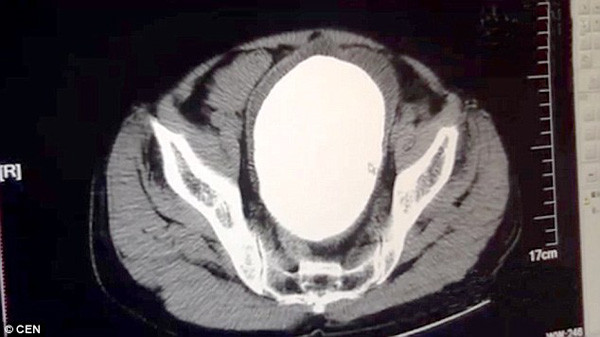

| Kết quả chụp x-quang viên sỏi trong túi mật ông Zhang Guolun. Ảnh: CEN |

Theo People"s Daily Online, viên sỏi hình giống như quả trứng, dài 14 cm, đã được lấy ra thành công khỏi túi mật của ông Zhang Guolun, 70 tuổi, sống ở huyện Luotian, tỉnh Hồ Bắc, hôm qua.